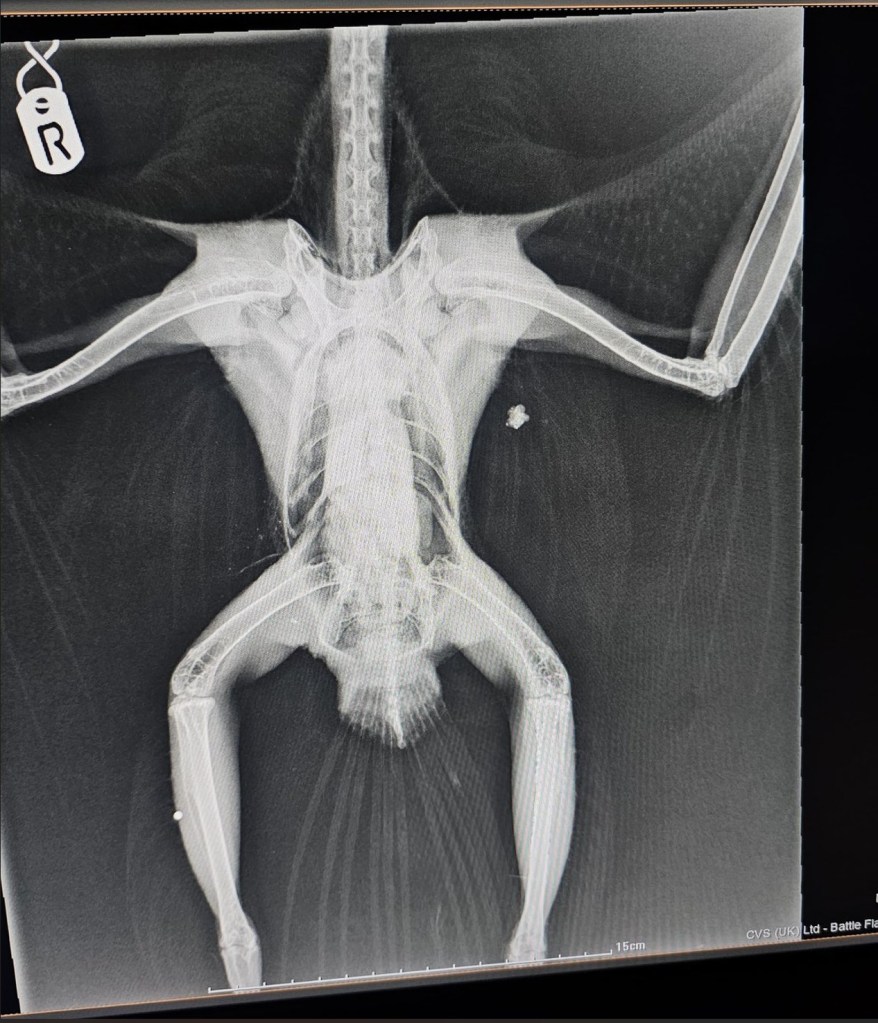

The Buzzard was taken to Battle Flatts Veterinary Clinic where an x-ray revealed a shotgun pellet lodged in her leg and associated feather damage.

The Buzzard was found on 25th January 2026. I think it must have been shot close to that date as the bird found it difficult to stand. She is standing now and was on a top perch this morning.